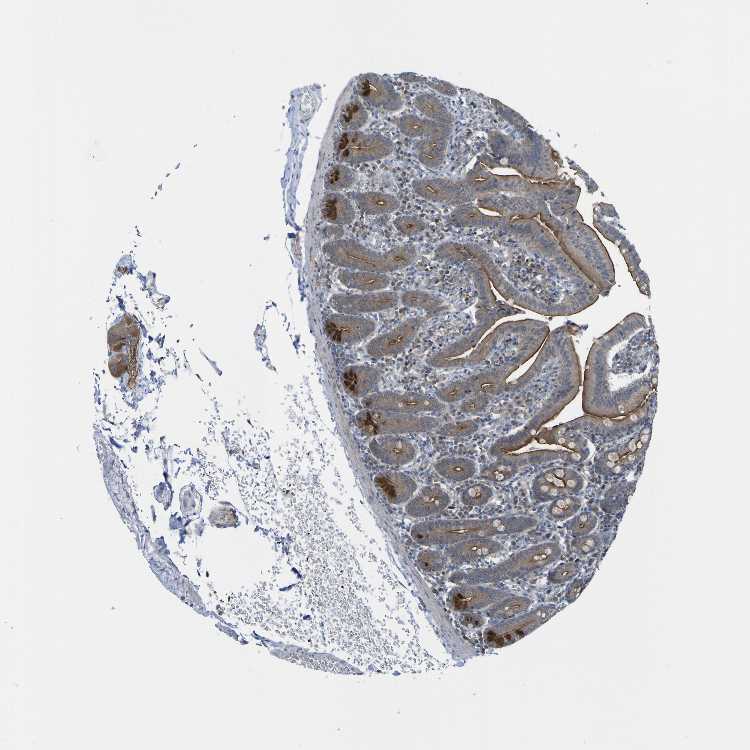

SMALL INTESTINE - Antibody stainingi

Antibody staining in the annotated cell types in the current human tissue is reported as not detected, low, medium, or high, based on conventional immunohistochemistry profiling in selected tissues. This score is based on the combination of the staining intensity and fraction of stained cells.

Each image is clickable and will lead to virtual microscopy that enables deeper exploration of all samples and also displays staining intensity scores, fraction scores and subcellular localization as well as patient and tissue information for each sample.

Antibody CAB010391

Glandular cells High